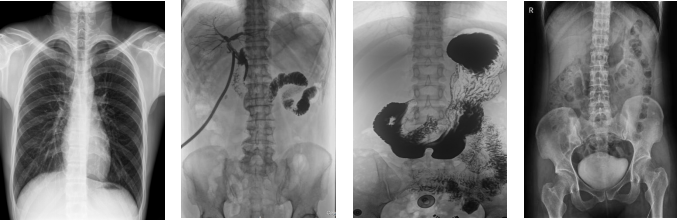

數(shù)字胃腸DR機(jī)是什么?數(shù)字胃腸DR機(jī)是用來(lái)檢查患者胃腸道疾病的X射線(xiàn)檢查設(shè)備,是醫(yī)院極為普遍的放射診斷影像設(shè)備之一。它是將傳統(tǒng)透視、數(shù)字化胃腸與DR攝像技術(shù)相結(jié)合,其圖像數(shù)字化采集,經(jīng)數(shù)字化處理后圖像更加清晰。接下來(lái)給大家介紹一款我公司主流的數(shù)字胃腸DR機(jī),看看它好在哪里。

PLD8000C數(shù)字胃腸DR機(jī)突破傳統(tǒng)X射線(xiàn)攝影透視理念,成像部件采用新型動(dòng)態(tài)平板探測(cè)器,輕松解決數(shù)字?jǐn)z影、數(shù)字透視、數(shù)字造影等功能,并使數(shù)字透視獲得超大尺寸和清晰的圖像效果。滿(mǎn)足放射科、體檢中心、影像中心、內(nèi)科、婦科、外科、急診科、骨科、創(chuàng)傷科、消化科等科室的各種臨床檢查需求。